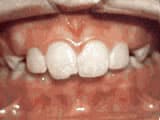

Open bite: front teeth don’t touch

Before

AfterThis girl sucked her thumb as a young child. She started treatment at age 13. She had braces and a special appliance — called a crib — to retrain the tongue, for 28 months. Now she can bite the lettuce out of a sandwich.